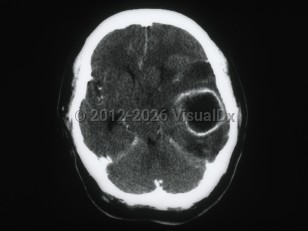

Subarachnoid hemorrhageSubarachnoid hemorrhage

Epidural intracranial hematomaEpidural intracranial hematoma

Posterior fossa hematoma